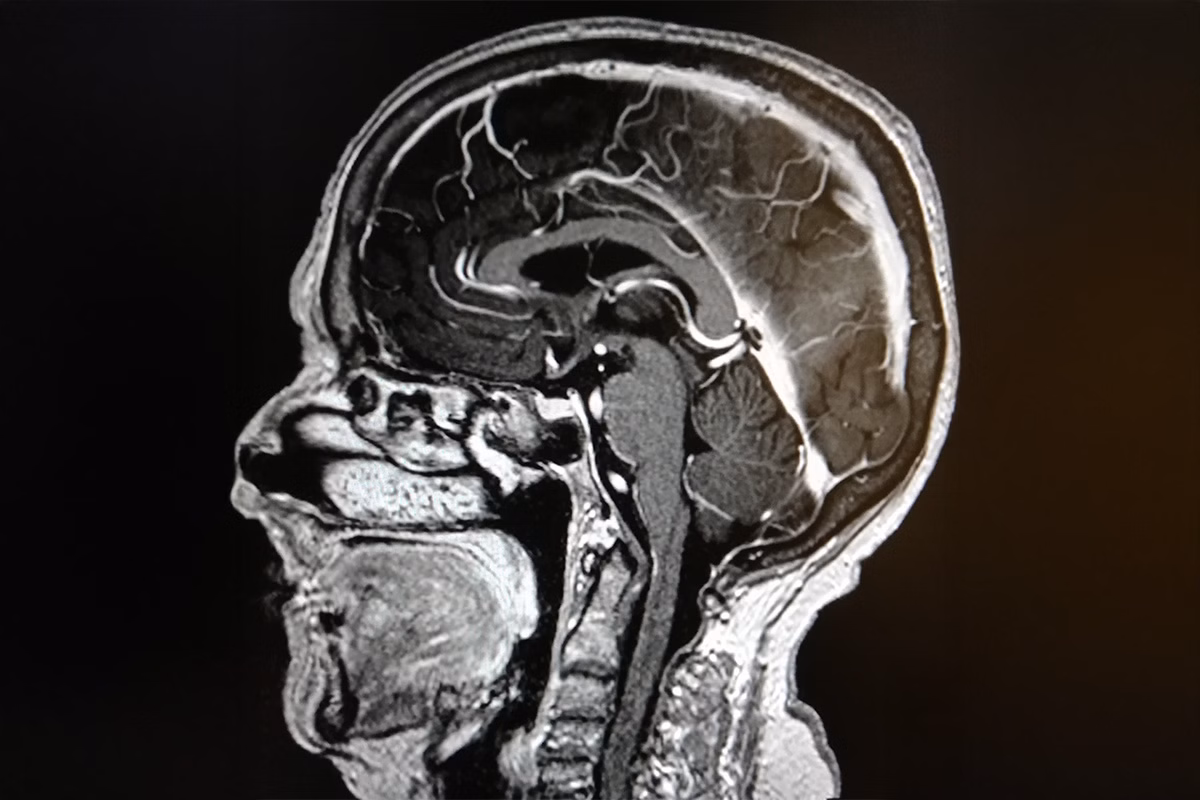

Wenn wir vom Wachzustand in den Schlaf übergehen, beginnt das Netzwerk in unserem Gehirn (das Retikularsystem), unsere Sinne schrittweise zu dämpfen. Normalerweise geschieht dies fließend. Bei einer EHS-Episode erleben die sensorischen Neuronen jedoch möglicherweise eine plötzliche und gleichzeitige elektrische Entladung. Es ist, als würde der Computer des Gehirns kurzzeitig abstürzen und neu starten, wodurch alle akustischen Reize als ein einziger, gewaltiger Impuls registriert werden.